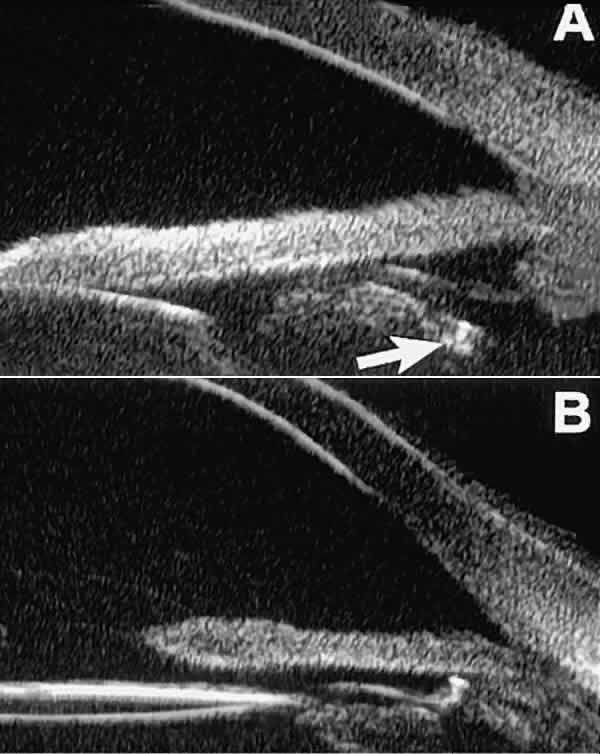

Postoperative UBM imaging of the anatomic changes caused by glaucoma surgery often helps to explain mechanisms of success and failure of the various surgical procedures (Fig. 12).3,4 After laser iridotomy, UBM can show whether the iridotomy is partial thickness (see Fig. 12A) or full thickness (see Fig. 12B) and whether the plane of curvature of the peripheral iris has changed compared with the pretreatment findings. After trabeculectomy (see Fig. 12C), UBM can show whether the scleral aperture is patent or blocked internally, whether the peripheral iridectomy is open or blocked, and whether the filtering bleb is flat, shallow, or deep.9 After tube shunt surgery (see Fig. 12D), UBM can show the position of the tip of the tube and whether its orifice is open or plugged.

Fig. 12. UBM features in glaucomatous eyes after treatment or filtering surgery. A. Incomplete peripheral iridectomy created by laser. B. Full-thickness peripheral iridectomy created by laser. C. Postoperative features of trabeculectomy including peripheral iridectomy, inner scleral defect, thin residual scleral flap, and overlying conjunctival filtering bleb. D. Tube shunt projecting radially into anterior chamber; note that the tube “shadows” deeper structures.